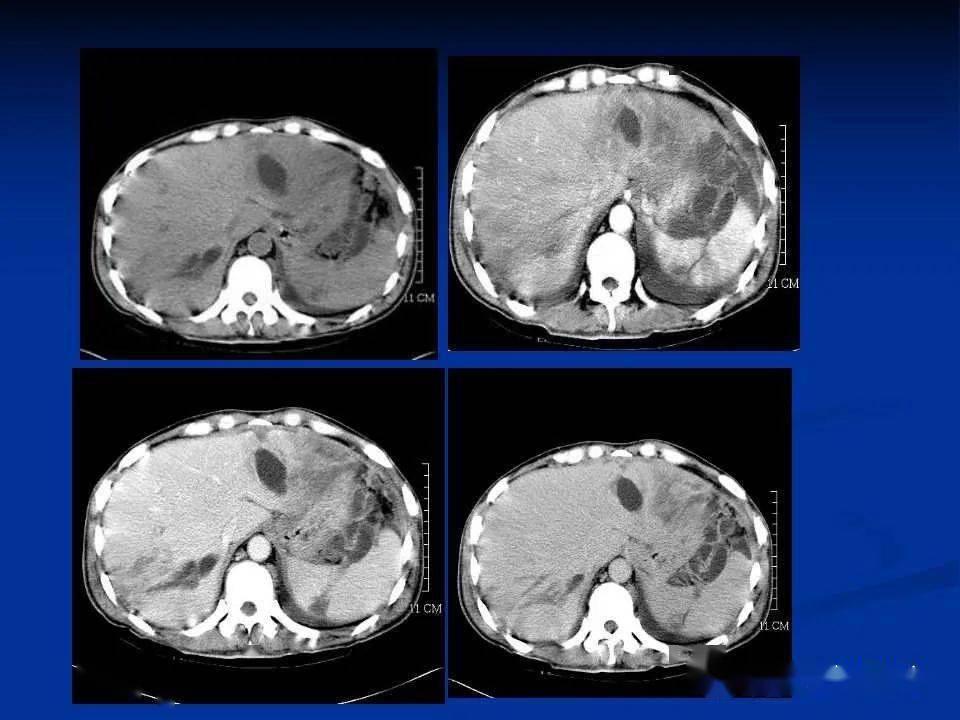

增强ct显示脾大,正常人脾脏约400g,而该患者的脾脏接近8-10斤,是一个

ct平扫 增强( 脾大,脾实质内多发点状钙化灶,未见异常强化灶)

强化ct可见脾周血管.脾下缘查体时脐下5厘米可触及.